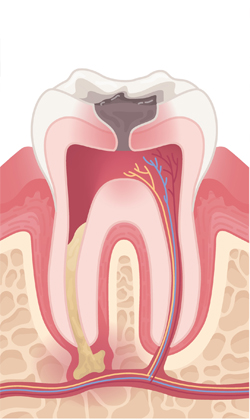

When a tooth is severely damaged or decayed, an infection can form and spread to the nerve tissue and pulp. To repair and save the tooth, a root canal treatment is performed by our endodontist. During the root canal procedure, the infected nerve and pulp are removed and the inside of the tooth is cleaned and sealed.

Some symptoms that can indicate the need for a root canal are persistent pain while chewing or biting, sensitivity to hot or cold, swollen or tender gums, tooth discoloration, chipped or cracked teeth, and pimples on the gums.

with abscess

An opening is made in the crown of the tooth.